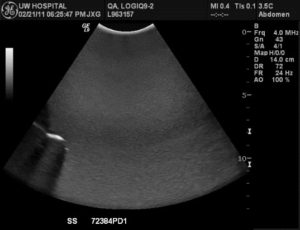

With basic B-mode imaging (shown below) two parameters of performance can be qualitatively assessed using a TMP; sensitivity (the ability to discern faint echoes) and uniformity (homogeneity of the echoes, see photo below, left). In addition to be a qualitative test this is also a subjective test as it relies on the visual acuity of the tester to detect small variances in the image. Using a TMP also is complicated by the desire (sometimes subconsciously) to make an image captured during today’s test “look” like the one that was captured during a previous test, usually by adjusting the TGC controls, gain, and various processing functions. Modern systems also have heavily averaged image processing algorithms such as Spatial Compounding that can mask transducer problems such as dead elements, as demonstrated in the image below, right. Lastly, because of the rather narrow range of gray scale visual acuity in humans the TMP test results can be misinterpreted by someone who may not be able to discern subtle differences in the image.

Spatial compounding masks subtle probe failures in this image with multiple dead elements in the array